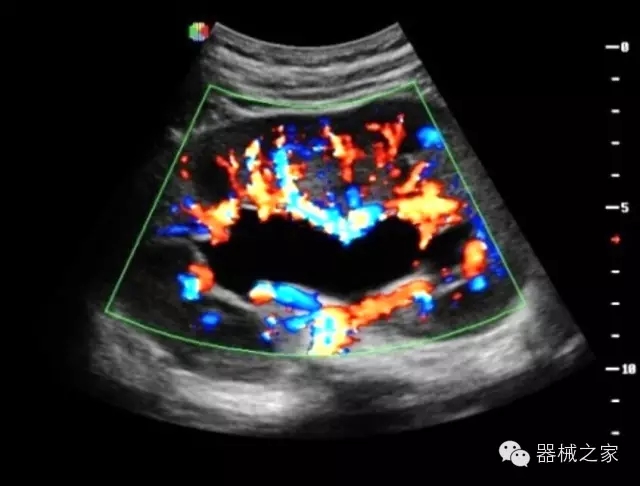

臨床圖片賞析

產(chǎn)品特點

·全球目前唯一一款配備主機雙探頭接口,整機重量(含電池)在5公斤以內(nèi)的便攜式彩超;

·一款互聯(lián)網(wǎng)彩超,只要有手機信號的地方就可以非常方便地實現(xiàn)遠程會診和病案調??;

·鎂鋁合金外殼,堅固可靠耐用;

·獨有的HoloTM PW 實時3取樣門PW成像技術,精確進行血管診斷;

·一鍵優(yōu)化B、Color、PW,Auto Doppler自動識別血管位置、偏轉角度等,提高工作效率;

·30°超廣角精細偏轉成像技術,更優(yōu)異的頻譜圖像;

·W+智能搜索引擎,快速尋找圖像;

·SSD、USB3.0保障開機快,導出圖像更快,減少等待時間;

·WIFI、網(wǎng)口、3G,多重聯(lián)網(wǎng)方式,全天候保障云端備份,不再擔心圖像丟失;